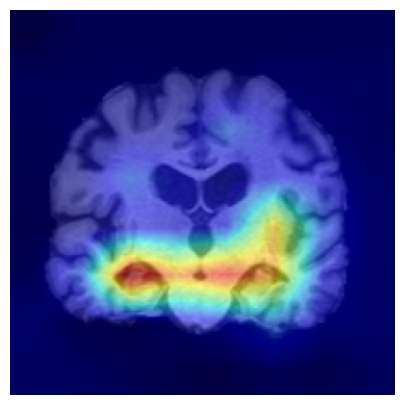

4.3.2 ADNI

We consider two groups constructed from the ADNI dataset based on hippocampal volume, a well-established neuroimaging biomarker of Alzheimer’s disease–related neurodegeneration. Each group includes 918 2D slices. Subjects exhibiting reduced hippocampal volume indicative of hippocampal atrophy are assigned to Group 1, while subjects with preserved hippocampal volume form Group 2. This stratification induces group differences associated with disease-relevant anatomical variation and provides a clinically meaningful setting for evaluating whether the proposed feature-level explanations highlight brain regions known to be implicated in Alzheimer’s disease/cognitive impairment.

We use a ResNet-50 encoder pretrained on the UK Biobank dataset, predicting the age of brains, and adapt this pretrained model using a linear probing strategy on the ADNI dataset. Specifically, we train a logistic regression layer on top of the frozen encoder to predict group membership, while keeping all encoder parameters fixed. After training, the linear head is discarded, and the frozen encoder is used to extract embeddings for two-sample testing and for generating feature-level explanations. We apply the proposed feature-level explanation method to individual MRI scans and assess whether the resulting attributions align with known disease-related neuroanatomical patterns.

To assess the robustness of our feature-level explanations, we apply multiple channel-aggregation strategies to the gradients of the test statistic: (i) gradient-weighted aggregation Selvaraju et al. (2017), (ii) second-order gradient aggregation Chattopadhay et al. (2018), and (iii) layer-wise spatial aggregation Jiang et al. (2021). Across all variants, the resulting heatmaps remain consistent. Additional details are provided in the Supplementary Material.

Results.

Figure 7 indicates the qualitative results. Our explainability method consistently highlights the hippocampal and medial temporal lobe regions, and the resulting heatmaps show strong correspondence with areas affected by hippocampal atrophy. These results supports that the identified regions align with established AD biomarkers.